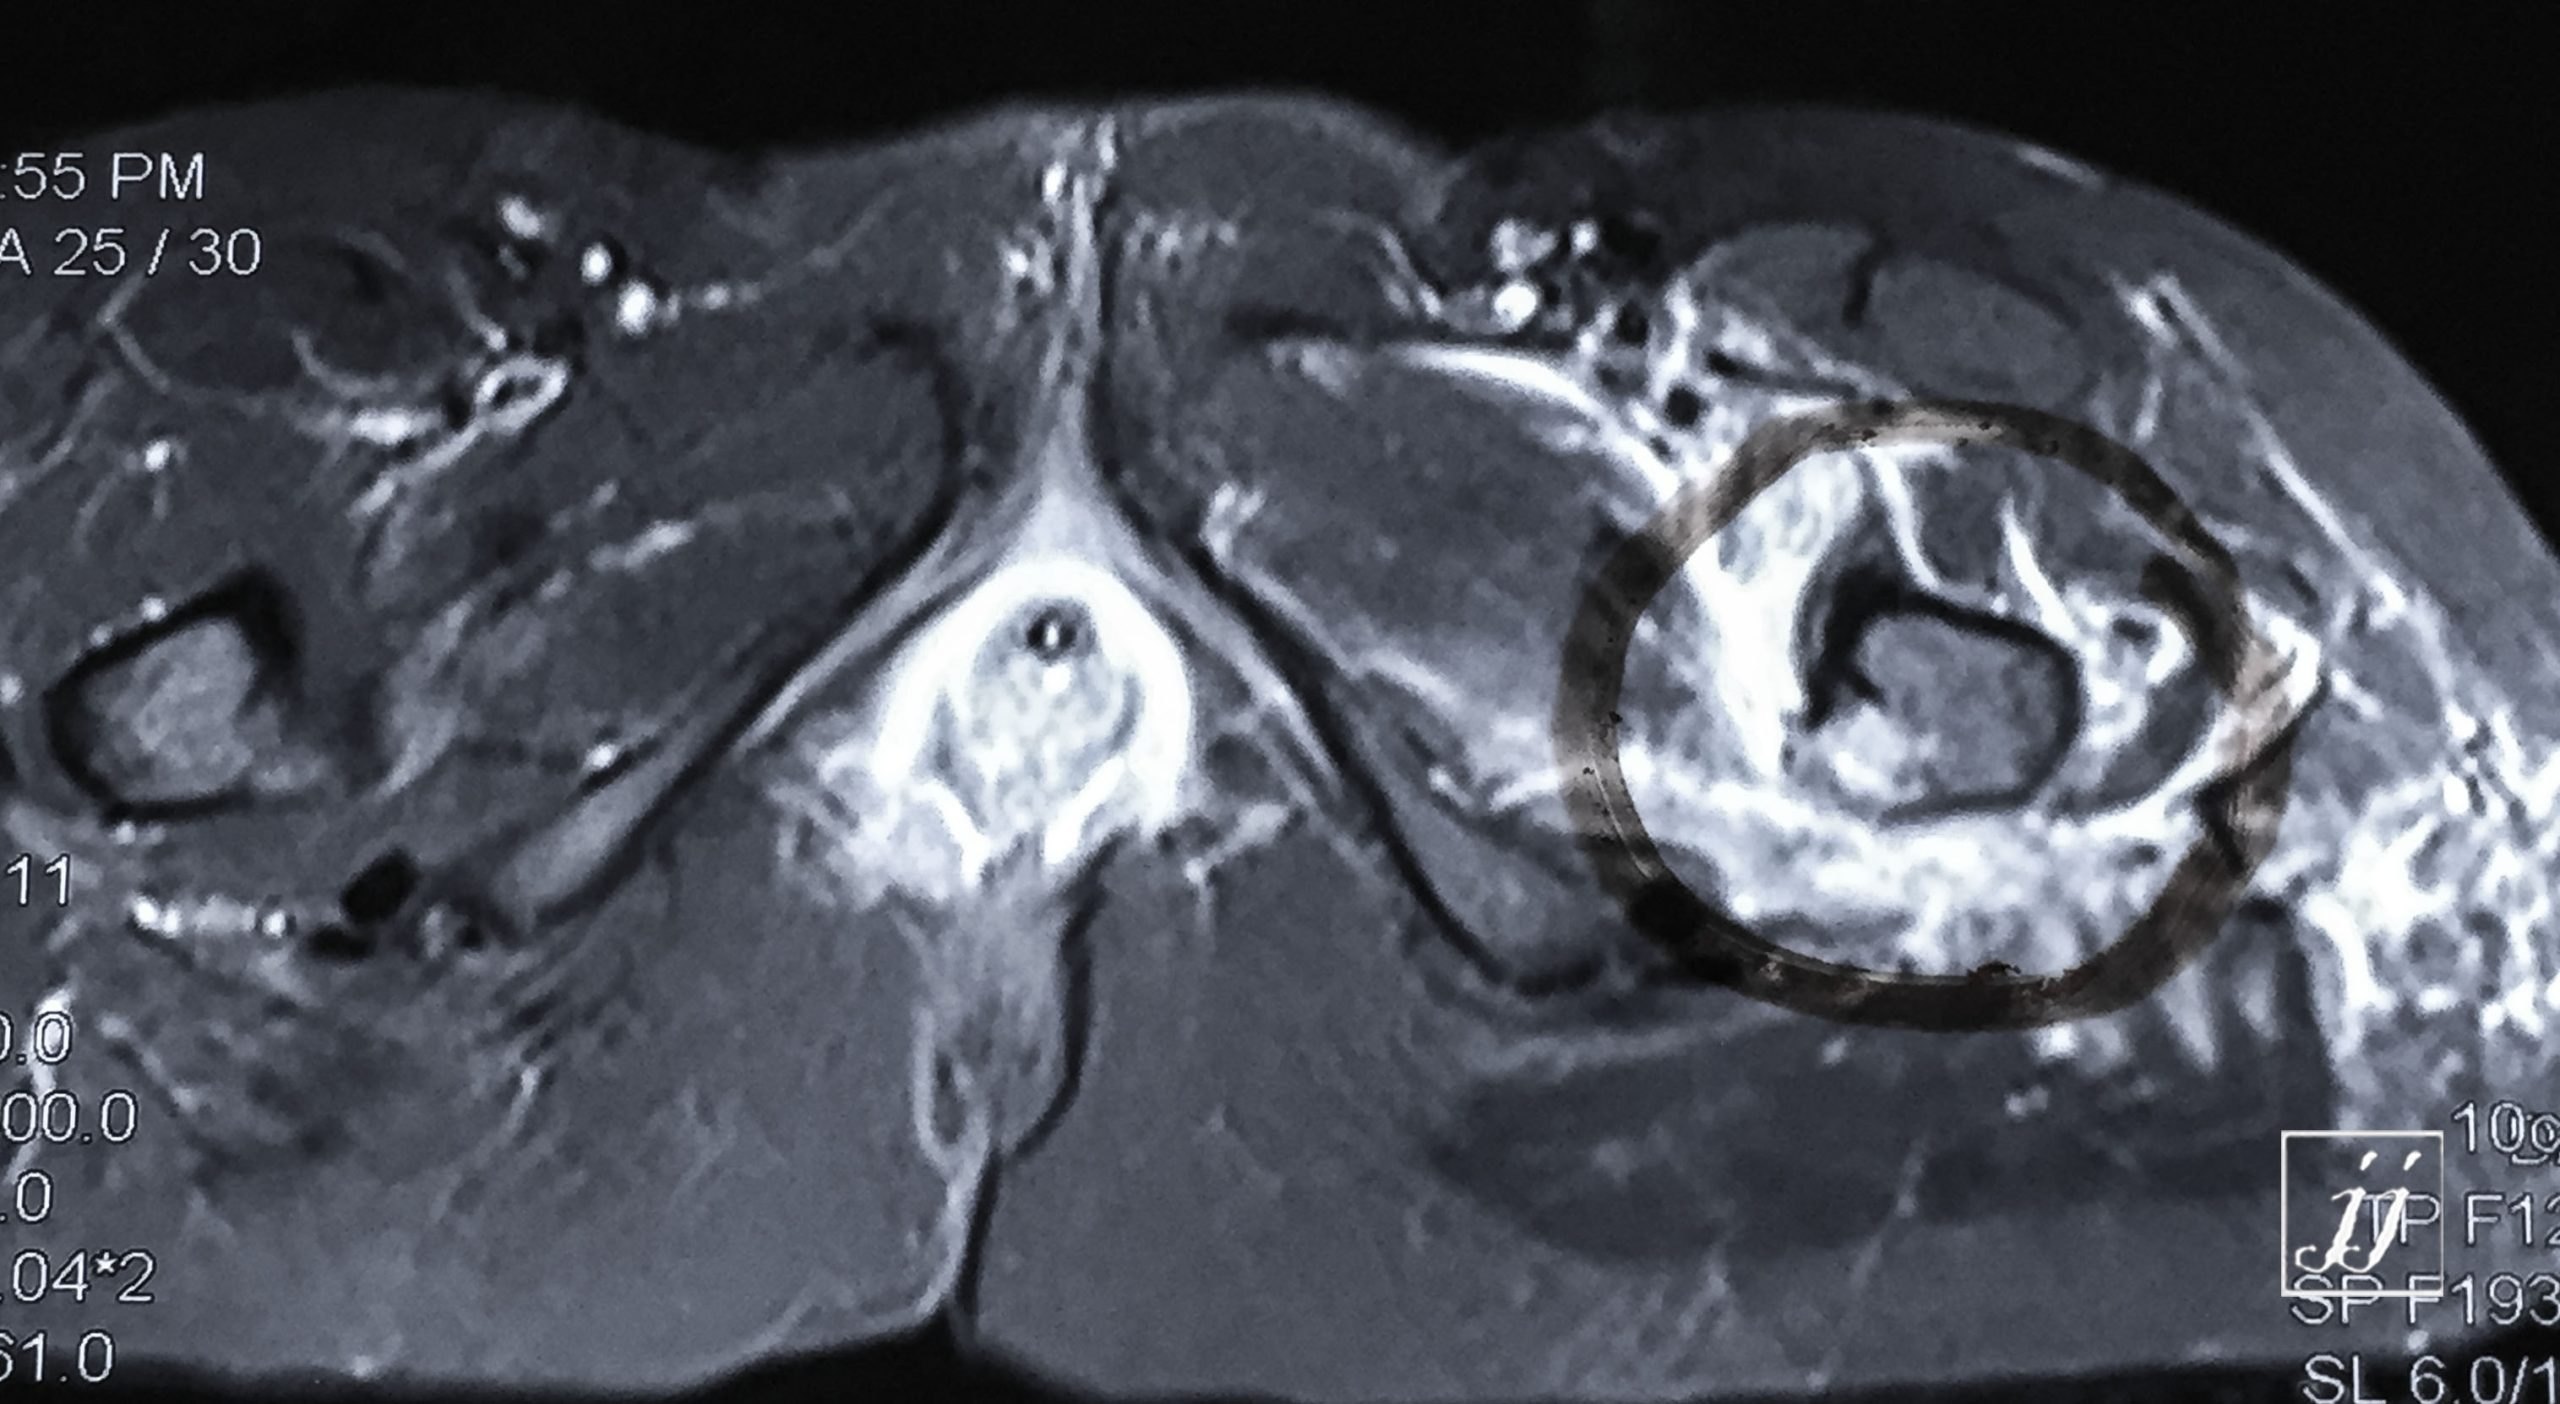

MSK- detached fracture of lesser trough chanter (27)